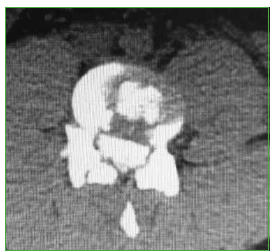

Figura 2.

Caso 1. Tomografía computarizada, corte axial.

El paciente es trasladado al Servicio de Urgencia del hospital regional y, de allí, es derivado a nuestro centro, a través de su obra social. Ingresa, reactivo, lúcido (escala de Glasgow 15/15), con estabilidad hemodinámica y síndrome de cauda equina incompleto (grado B según el puntaje de la ASIA).19 Se solicitan radiografías y TC de columna cervical, torácica y lumbosacra. Se constata fractura vertebral lumbar baja con compromiso de la cuarta vértebra lumbar (L4), de tipo estallido, con retropulsión de un fragmento voluminoso del muro posterior en el canal, con impronta en el saco dural. La resonancia magnética no mostró una lesión del complejo ligamentario posterior, por lo que se interpreta, según la clasificación AO, como L4: A3, N3, M0 (Figuras 2 y 3). Sin deformidad en cifosis significativa y con un colapso vertebral inferior al 50%. Se constata una lesión hepática asociada, se lo somete a una laparotomía de urgencia y queda internado en la Unidad de Terapia Intensiva.